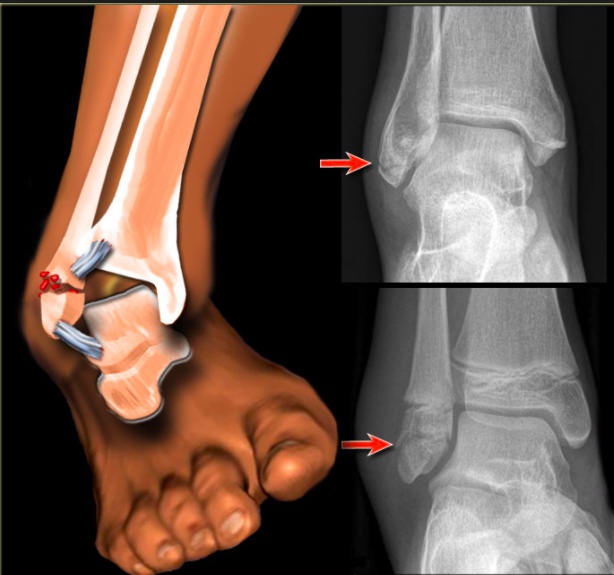

Ankle

Ankle fractures include fractures of the medial, lateral, and/or posterior malleoli.

Medial malleolus fractures are generally the result of an eversion injury whereas lateral malleolus fractures are the result of an inversion injury.

lateral malleolus:

medial malleolus:

These fractures commonly occur in athletes and as a result of trauma.

Non displaced ankle fractures are treated with a cast, but displaced or unstable fractures require open reduction internal fixation.